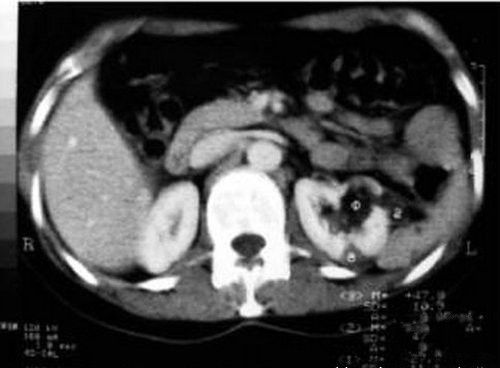

哈尔滨一家出租汽车公司的张云兵一直自觉精力充沛,干活不累,并未感到与常人有什么不同。后来,他因“腰痛”在哈尔滨市一医院泌尿科检查会诊,医生发现他长有4个肾、4条输尿管。左肾里有一结石正是导致这次肾绞痛的原因。